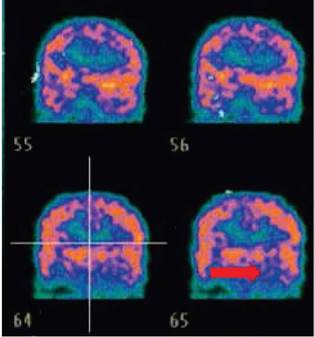

Tomografía por emisión de positrones. Tomografía por emisión de positrones (PET-CT). Indicador señala alteraciones en el metabolismo en región temporal izquierda. Tomado de soportes de historia clínica provistos por la acudiente de la paciente.

Figura 1: Tomografía por emisión de positrones. Tomografía por emisión de positrones (PET-CT). Indicador señala alteraciones en el metabolismo en región temporal izquierda. Tomado de soportes de historia clínica provistos por la acudiente de la paciente.

Durante el estudio de la epilepsia se solicitaron múltiples paraclínicos que incluyeron, además de resonancia magnética cerebral con espectroscopia cuyo resultado fue normal, una nueva telemetría de 96 horas que mostró 3 crisis focales (figura 2) con actividad epileptiforme frontal bilateral con predominio basal derecho y generalización secundaria. Se realizó PET-CT que evidenció moderada a severa disminución del metabolismo en región temporal izquierda. Adicionalmente se hizo estudio completo de inmunodeficiencias y enfermedades metabólicas que cuáles fueron negativos (figura 3).